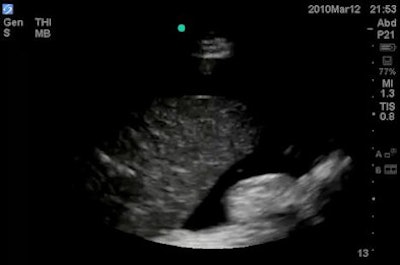

A standard ultrasound protocol for hypotension was employed, including a cardiac study (encompassing ejection fraction estimation, right ventricular [RV] dilation, and the presence or absence of pericardial effusion and tamponade), inferior vena cava (IVC) diameter measurement, a FAST (focused assessment with sonography for trauma) exam, an aorta scan (to check for abdominal aortic aneurysm), and a thoracic study (to detect pneumothorax).

In other findings, Shokoohi reported that ultrasound found abnormal IVC diameter in 46% of patients, abnormal ejection fraction in 36%, RV dilation in 14%, peritoneal and pleural free fluid in 13%, pericardial effusion in 8%, tamponade in 1.4%, and abdominal aortic aneurysm in 1.4%. No pneumothorax cases were found.

While ultrasound did not have a clinically significant impact in 49% of patients, Shokoohi noted that in a small number of cases, ultrasound yielded dramatic changes in diagnosis and management.

"In this minority of cases, you find the diagnosis [with ultrasound] that none of us can afford to miss," Shokoohi said.